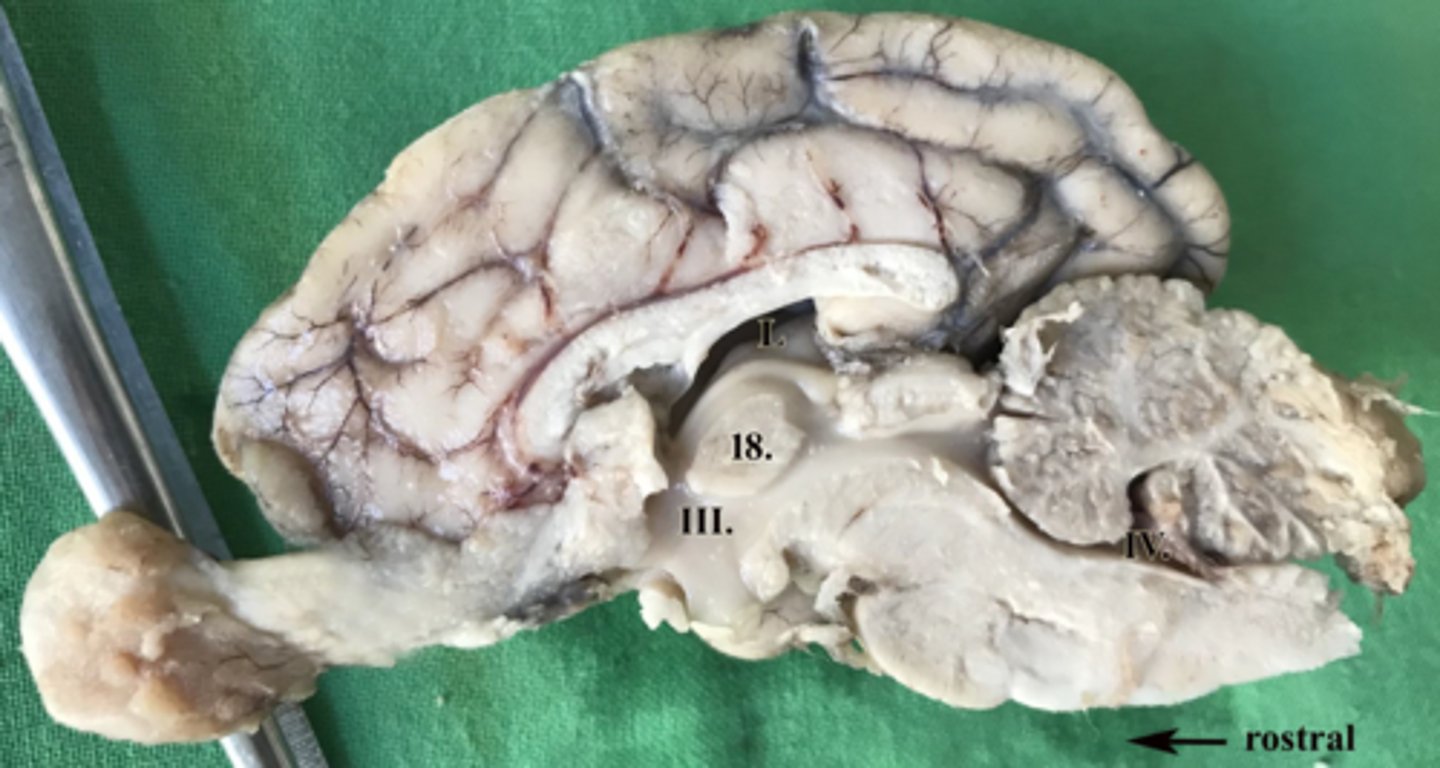

ventriculus tertius

III

ventriculus quartus

IV

adhesio interthalamica

18

ventriculus lateralis

L